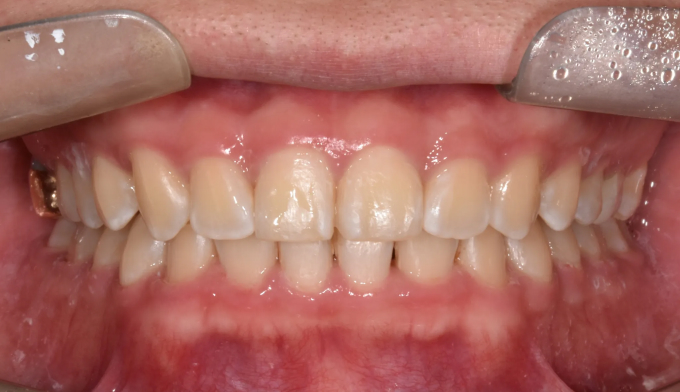

과개교합

과개교합은 앞니를 잇몸안으로 집어넣거나 반대로 어금니를 잇몸밖으로 빼내어 치료하는 방법이 있습니다.

환자의 안모 형태와 입술 두께등을 종합적으로 고려하여 치료방법을 결정합니다.

본 케이스에서는 치아 노출도를 고려하여 윗니를 위로, 아랫니를 아래로 함입하여 과개교합을 치료하였습니다.

교정기간은 총 10개월입니다.